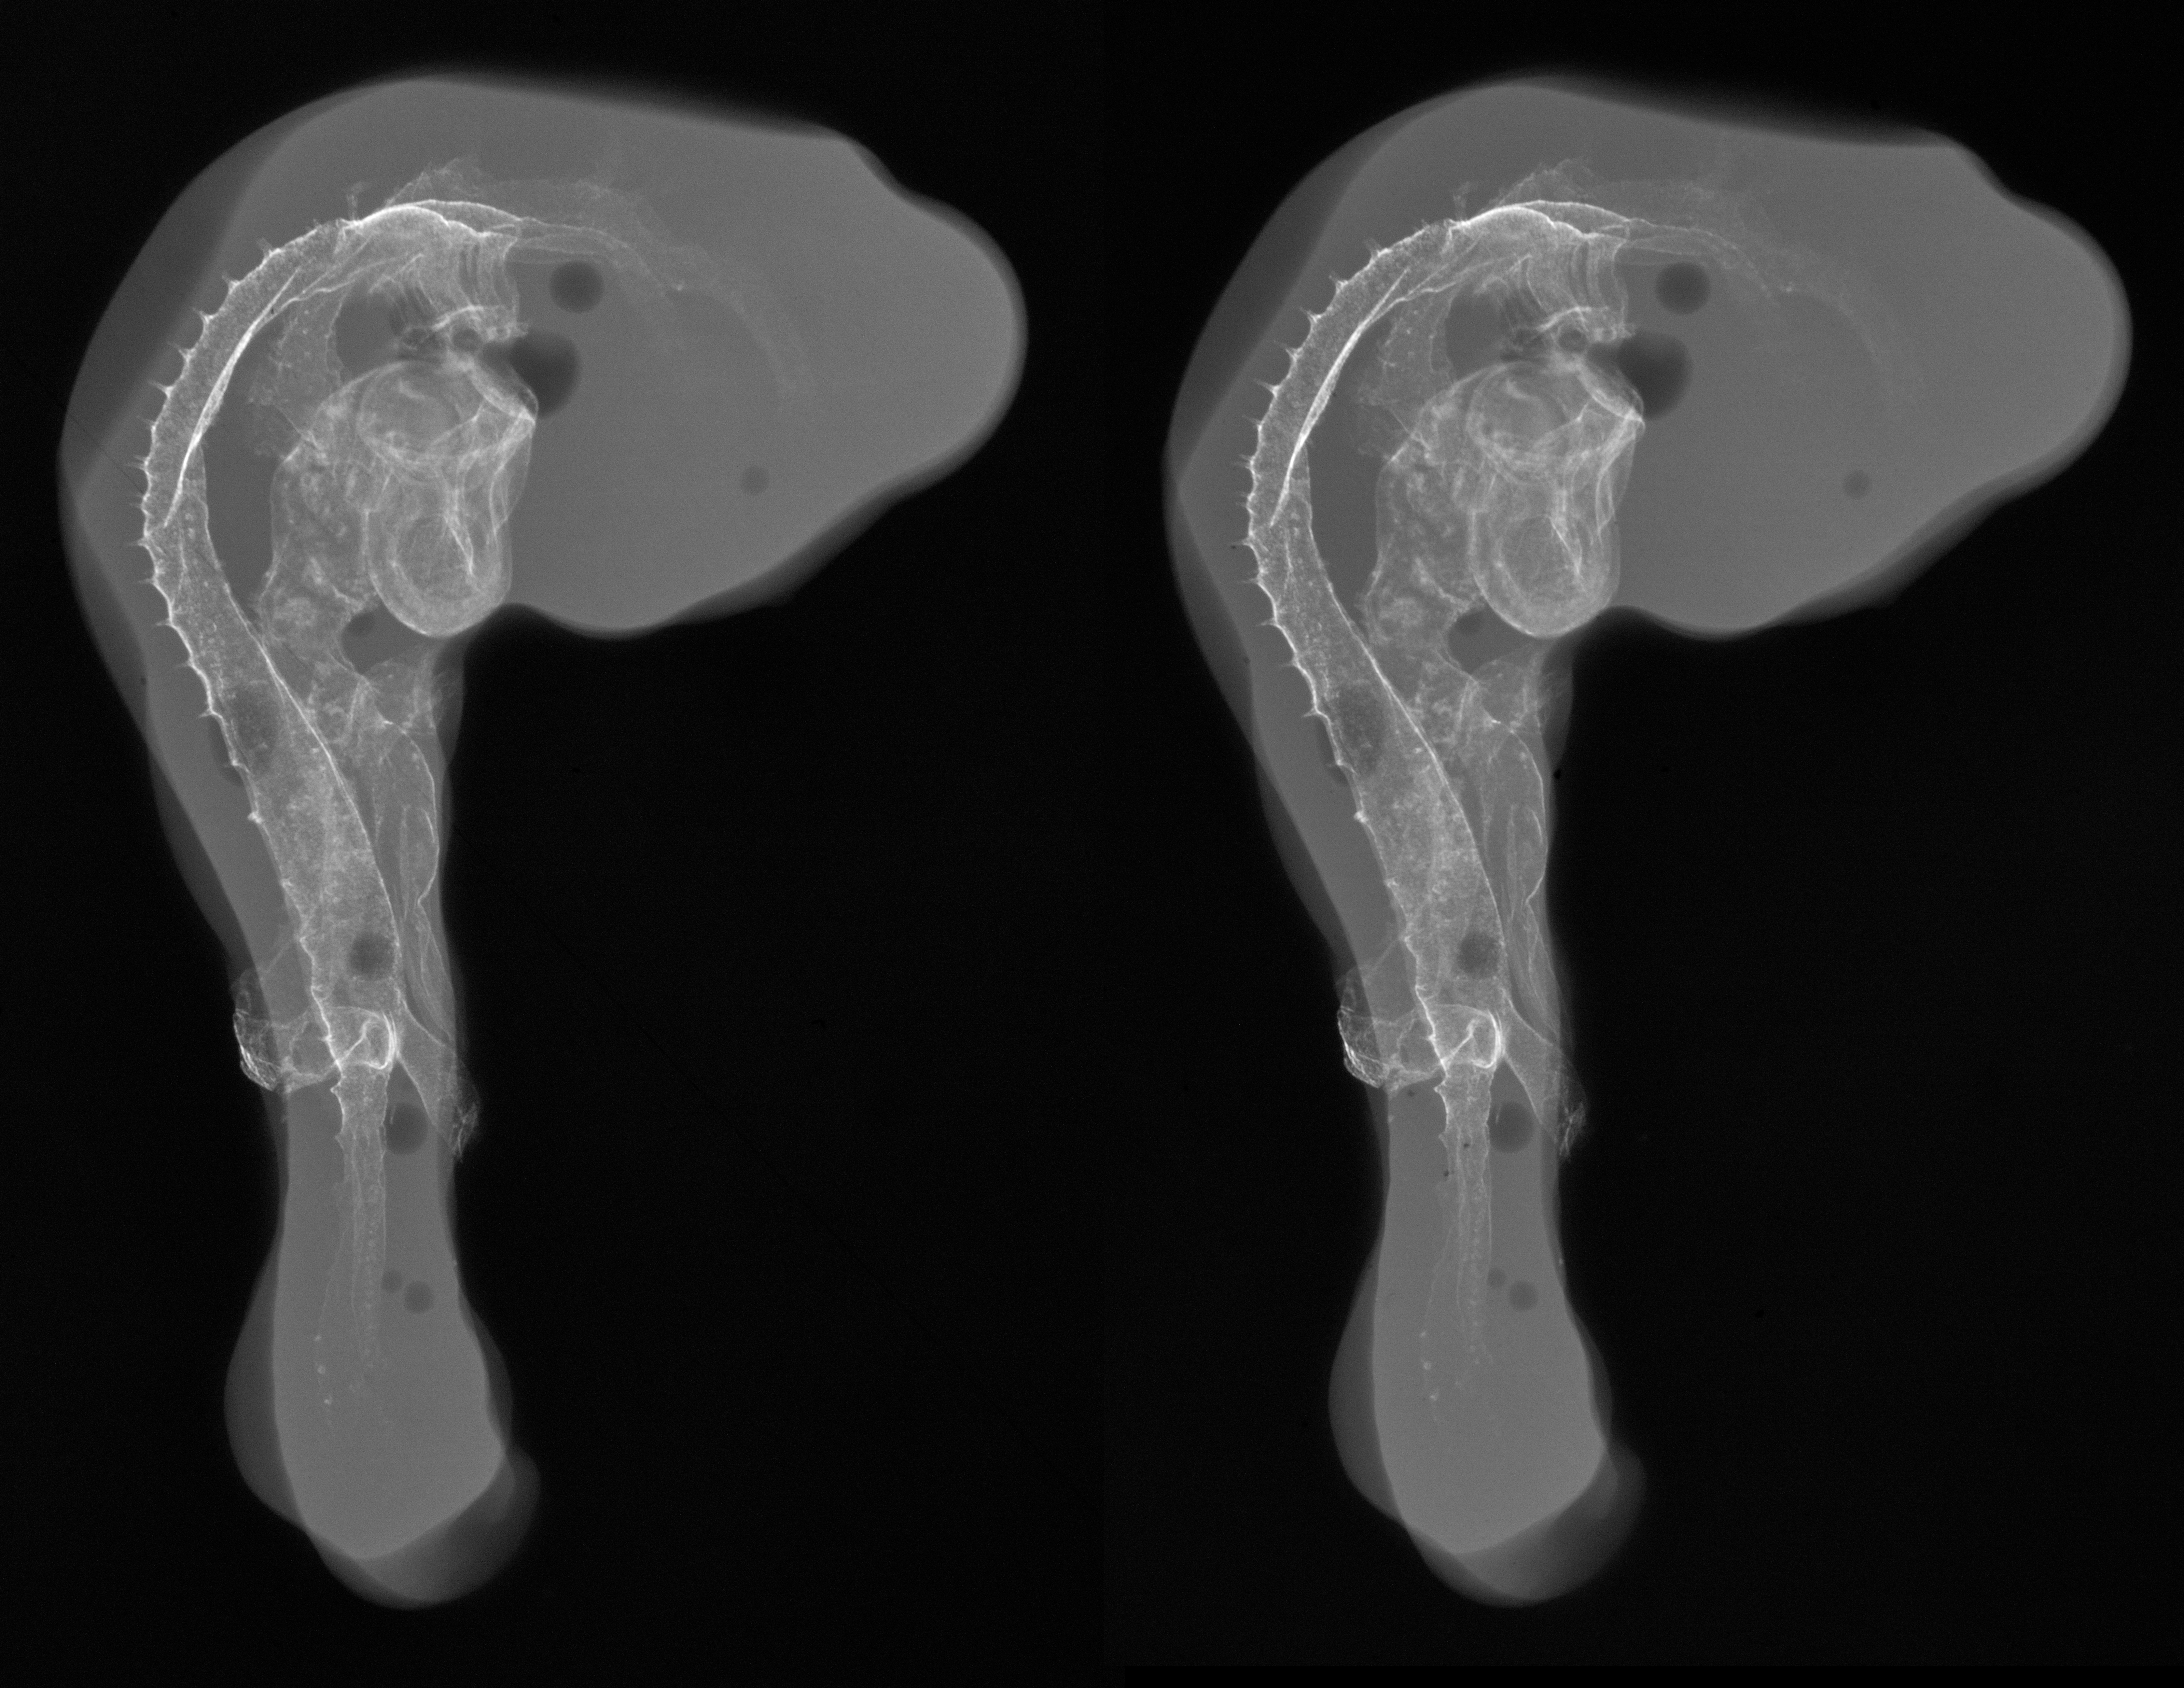

Chick Embryo Microangiography

Hamburger-Hamilton (HH) Stage 20 (approx. 3 - 3.5 days)

Stereo X-Ray Micrographs